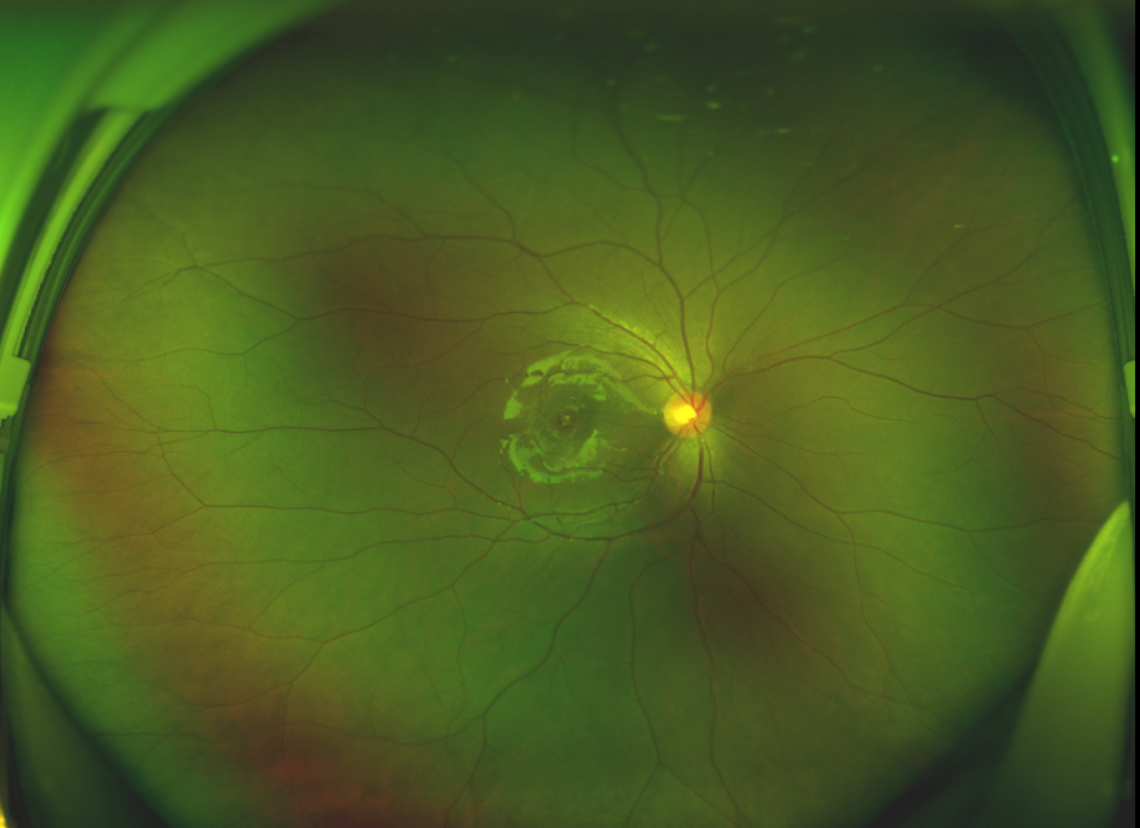

半年前的一次意外,誠(chéng)誠(chéng)(化名)右眼不慎受傷導(dǎo)致黃斑裂孔。從此,他的“視”界不再清晰,也不再有直線條……

黃斑位于視網(wǎng)膜正中心,是視覺(jué)最敏銳的區(qū)域,堪稱“眼底的心臟”,負(fù)責(zé)我們閱讀、駕駛、識(shí)別人臉等精細(xì)視覺(jué)。 當(dāng)黃斑區(qū)的神經(jīng)組織出現(xiàn)全層缺損,形成一個(gè)“孔洞”,即為黃斑裂孔,它會(huì)直接導(dǎo)致中心視力急劇下降、視物變形、視野中心出現(xiàn)暗區(qū)。

經(jīng)過(guò)詳細(xì)的檢查和評(píng)估,王曉波主任決定采用“內(nèi)界膜翻轉(zhuǎn)覆蓋聯(lián)合粘彈劑固定術(shù)”為誠(chéng)誠(chéng)進(jìn)行治療。

術(shù)中,醫(yī)生精細(xì)剝離黃斑區(qū)的內(nèi)界膜后,并非直接丟棄,而是巧妙地給它翻個(gè)面,讓它變成一塊天然“創(chuàng)可貼”,嚴(yán)密覆蓋在黃斑裂孔的表面。覆蓋的內(nèi)界膜像微型支架一樣撐住裂孔邊緣,防止它擴(kuò)大;同時(shí),這層膜本身含有能促進(jìn)生長(zhǎng)的“養(yǎng)分”,能顯著刺激裂孔周圍的視網(wǎng)膜組織像爬山虎一樣快速生長(zhǎng)、蔓延過(guò)來(lái),最終把裂孔“補(bǔ)”好。

除此之外,利用自體組織覆蓋為黃斑裂孔提供了理想的愈合環(huán)境,裂孔閉合速度顯著快于傳統(tǒng)方法。誠(chéng)誠(chéng)接受手術(shù)24小時(shí)后,檢查可見內(nèi)界膜瓣位置良好;術(shù)后1個(gè)月,黃斑裂孔已經(jīng)閉合,視力恢復(fù)到0.5;術(shù)后兩個(gè)月,視力進(jìn)一步提升到0.7。